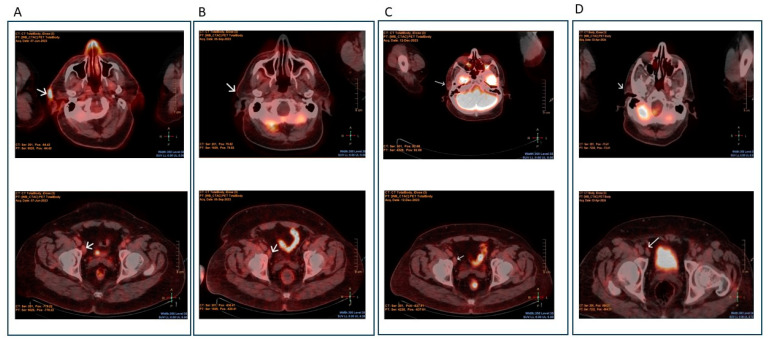

Background/objectives: The outcome of refractory/relapsed systemic Anaplastic Large Cell Lymphoma (R/R-sALCL), especially for anaplastic lymphoma kinase-1 (ALK-1)-negative disease, remains dismal even after autologous hematopoietic stem cell transplantation (AHSCT). The intensification of both salvage and conditioning regimens, without increasing the toxicity, could improve the outcome of AHSCT in R/R-sALCL. Methods: Based on the successful experience of the incorporation of antiD20 monoclonal antibodies in the treatment of B-Cell Lymphomas, we designed a salvage and conditioning regimen incorporating the antiCD30-conjugated antibody (Brentuximab Vedotin, BV) to standard chemotherapy regimens, and we describe herein the clinical course of a patient with AKL-ve, R/R-sALCL, who received salvage regimen BV + DHAP, followed by AHSCT with preparative regimen consisted of BV plus standard BEAM. Results: The novel regimen was well tolerated, and no severe adverse effects were noticed. The engraftment was prompt and successful. The patient remained in complete metabolic remission for almost 12 months post-transplant. Conclusions: The proposed treatment approach, which combines antiCD30-conjugated antibody with standard salvage and conditioning regimens, demonstrated a completely acceptable toxicity with promising efficacy.